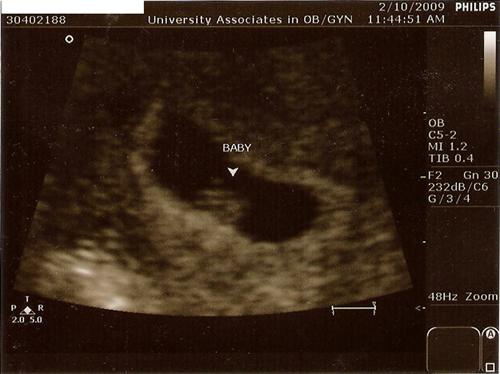

I went for my 1st sono today. We got to see and hear the heartbeat. It was so cool! I was so worried but the tech said everything looks great. I didn't even have to do an internal.

Here's our little blueberry:

7wk 2days